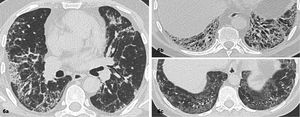

Patrón sugerente de otro diagnósticoCuando las características radiológicas sugieren una enfermedad diferente a UIP/IPF. En este caso es útil que el radiólogo proponga diferentes alternativas diagnósticas (figuras 5.1 y 5.2).

Enfermedad pulmonar interticial difusa con patrón sugerente de neumonía intersticial inespecífica (NII). Imágenes seleccionadas de TC de tórax en el plano axial, ventana pulmonar de dos pacientes

Áreas de densidad en vidrio esmerilado, reticulaciones y bronquiectasias por tracción de predominio basal y peribroncovascular. 6c. Respecto subpleural paravertebral basal bilateral.